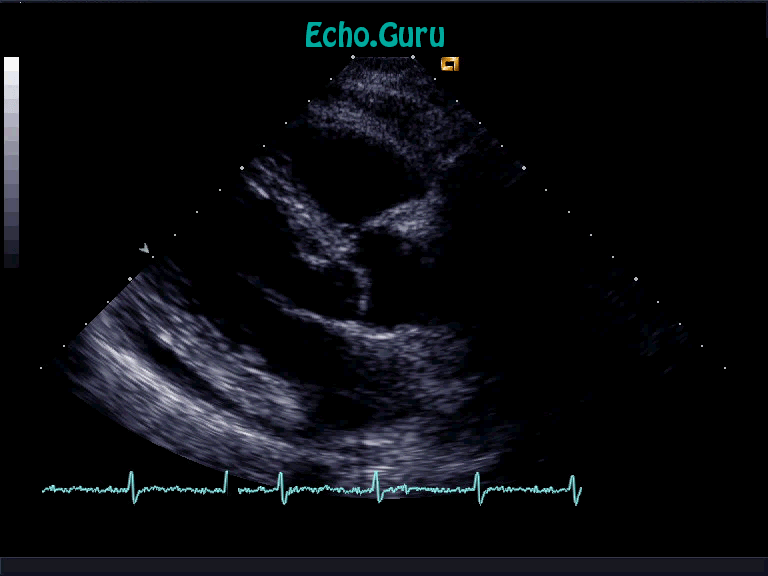

What is going on here?

Pericardial effusion